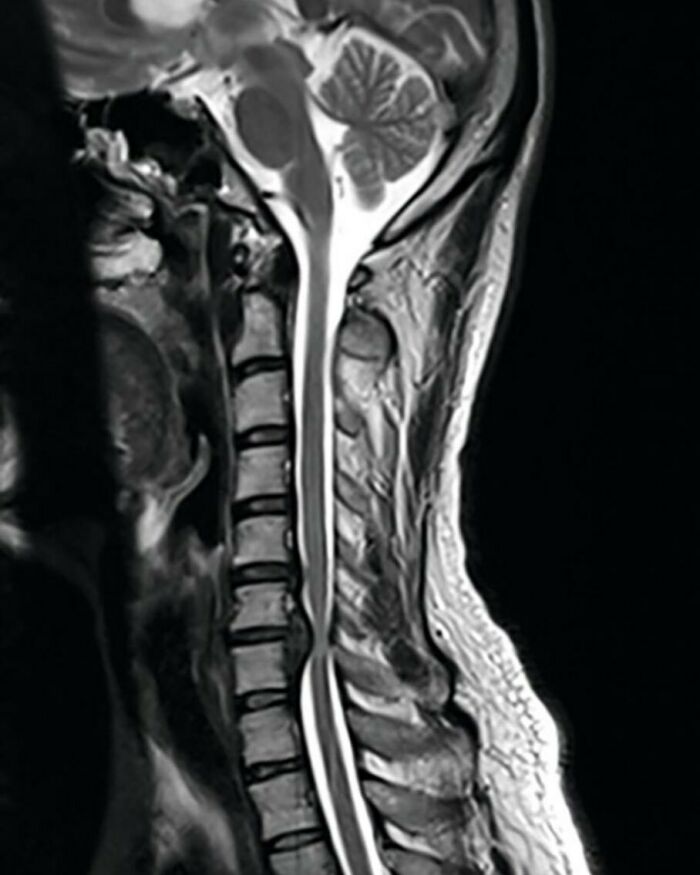

#26

MRI of spinal cord (sagittal view) showing vertebral disc herniation and spinal cord compression at the level of C6-C7